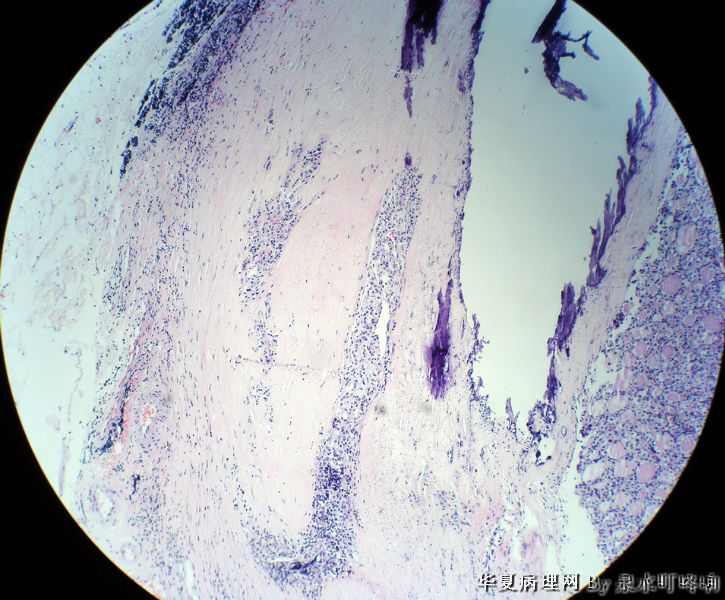

120212,女,55岁,左颈部肿物七年余。

大体:灰白肿物一个,大小约2.1×1.5×1.3厘米。表面光滑,包膜完整,切面灰白,部分包膜有钙化。

与手术医生沟通,肿物位于左颈部靠近甲状腺部位,比较浅(门诊手术),手术医生认为是淋巴结部位。

厚包膜、蕈状浸润----滤泡癌。

甲状腺滤泡性肿瘤,可见包膜及血管侵犯,考虑滤泡癌。

甲状腺滤泡状癌,有包膜浸润及血管内瘤栓

会诊结果:(颈左)考虑为甲状腺滤泡亚型乳头状癌,请结合临床进一步确认。